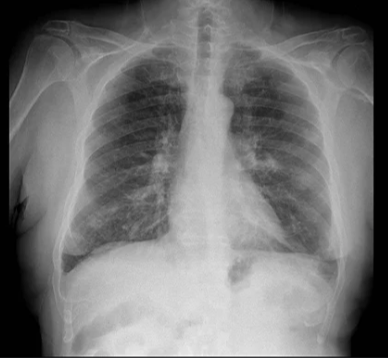

Rx de asma

Hiperclaridad

Engrosamiento bronquial

Q

Rx asma